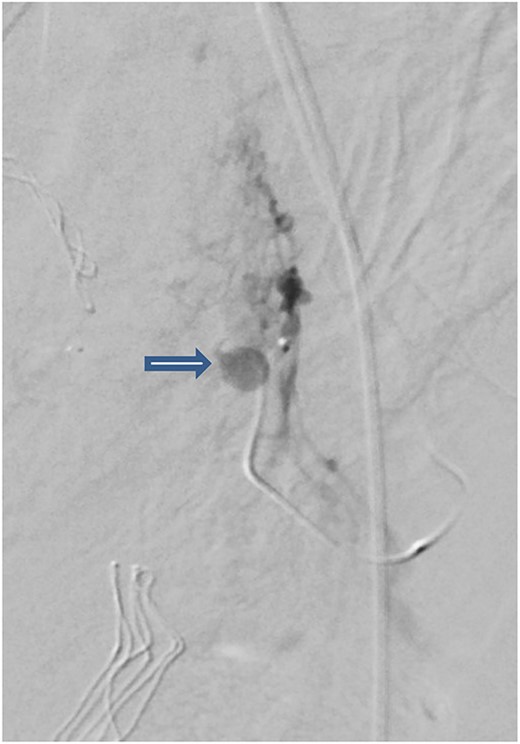

The case was again discussed between trauma and obstetric teams for possible need for interventional radiology consultation. Angiogram showed tortuous arteries with parenchymal blush in the right side of uterine wall, which was related to postpartum status. Gelfoam embolization of the right uterine artery was done to reduce the flow. On the other side, angiogram detected a pseudoaneurysm measuring ~7 mm (Fig. 3). Multiple vortex coils were used to obliterate the feeding vessels and post embolization angiogram showed satisfactory results (Fig. 4).

Post embolization angiogram showed satisfactory results after multiple Vortex coils were used to obliterate of feeding vessels.